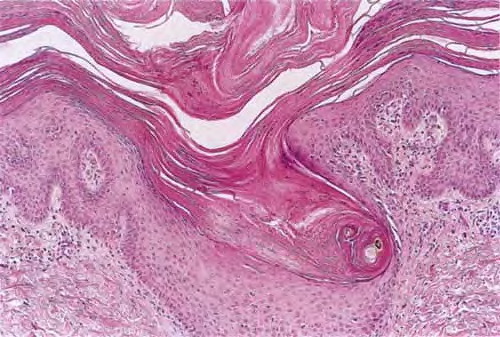

An orthokeratotic keratin plug blocks and dilates the orifice and upper portion of the follicular infundibulum . A twisted hair shaft may be trapped within this keratin material, and mild perivascular mononuclear cell infiltrates are usually present in the adjacent dermis.

A similar condition, lichen spinulosus , shows a very similar histologic picture except that the keratin plug may protrude more substantially above the skin surface and contain one or more hair shafts . Lesions similar to keratosis pilaris may also be seen in phrynoderma , but the follicular keratin plug is said to be parakeratotic .